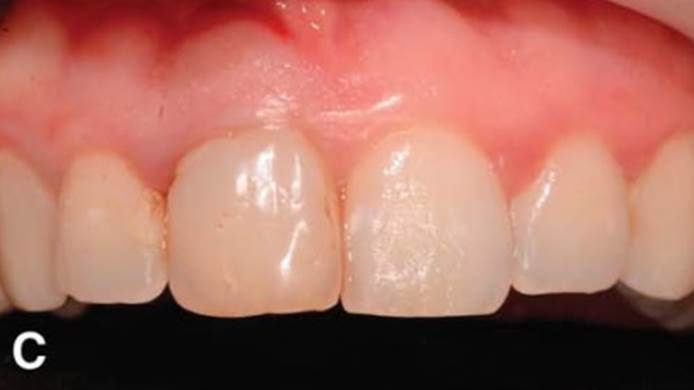

Clinical case: Replacement of fractured central incisor (#11) with immediate implant

& Root Membrane Technique

- Courtesy of Dr. Miltiadis Mitsias, Greece -

Keywords

AnyRidge, Root Membrane Technique, retrospective study, long-term study, immediate implants, bone resorption, bone preservation, Dr. Miltiadis Mitsias,survival, success, maxillary anterior, single replacement

Products:

AnyRidge implant system, Root Membrane kit